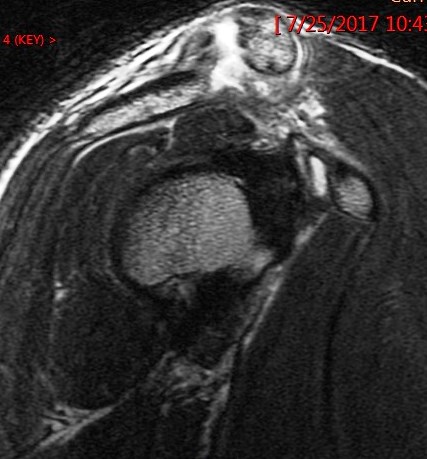

Figure 1 for case Grade 3 AC separation ( RID1895 )

Figure 1

The CC ligament is torn and the distal clavicle is elevated. Reference article.

Grade 3 AC separation ( RID1895 )